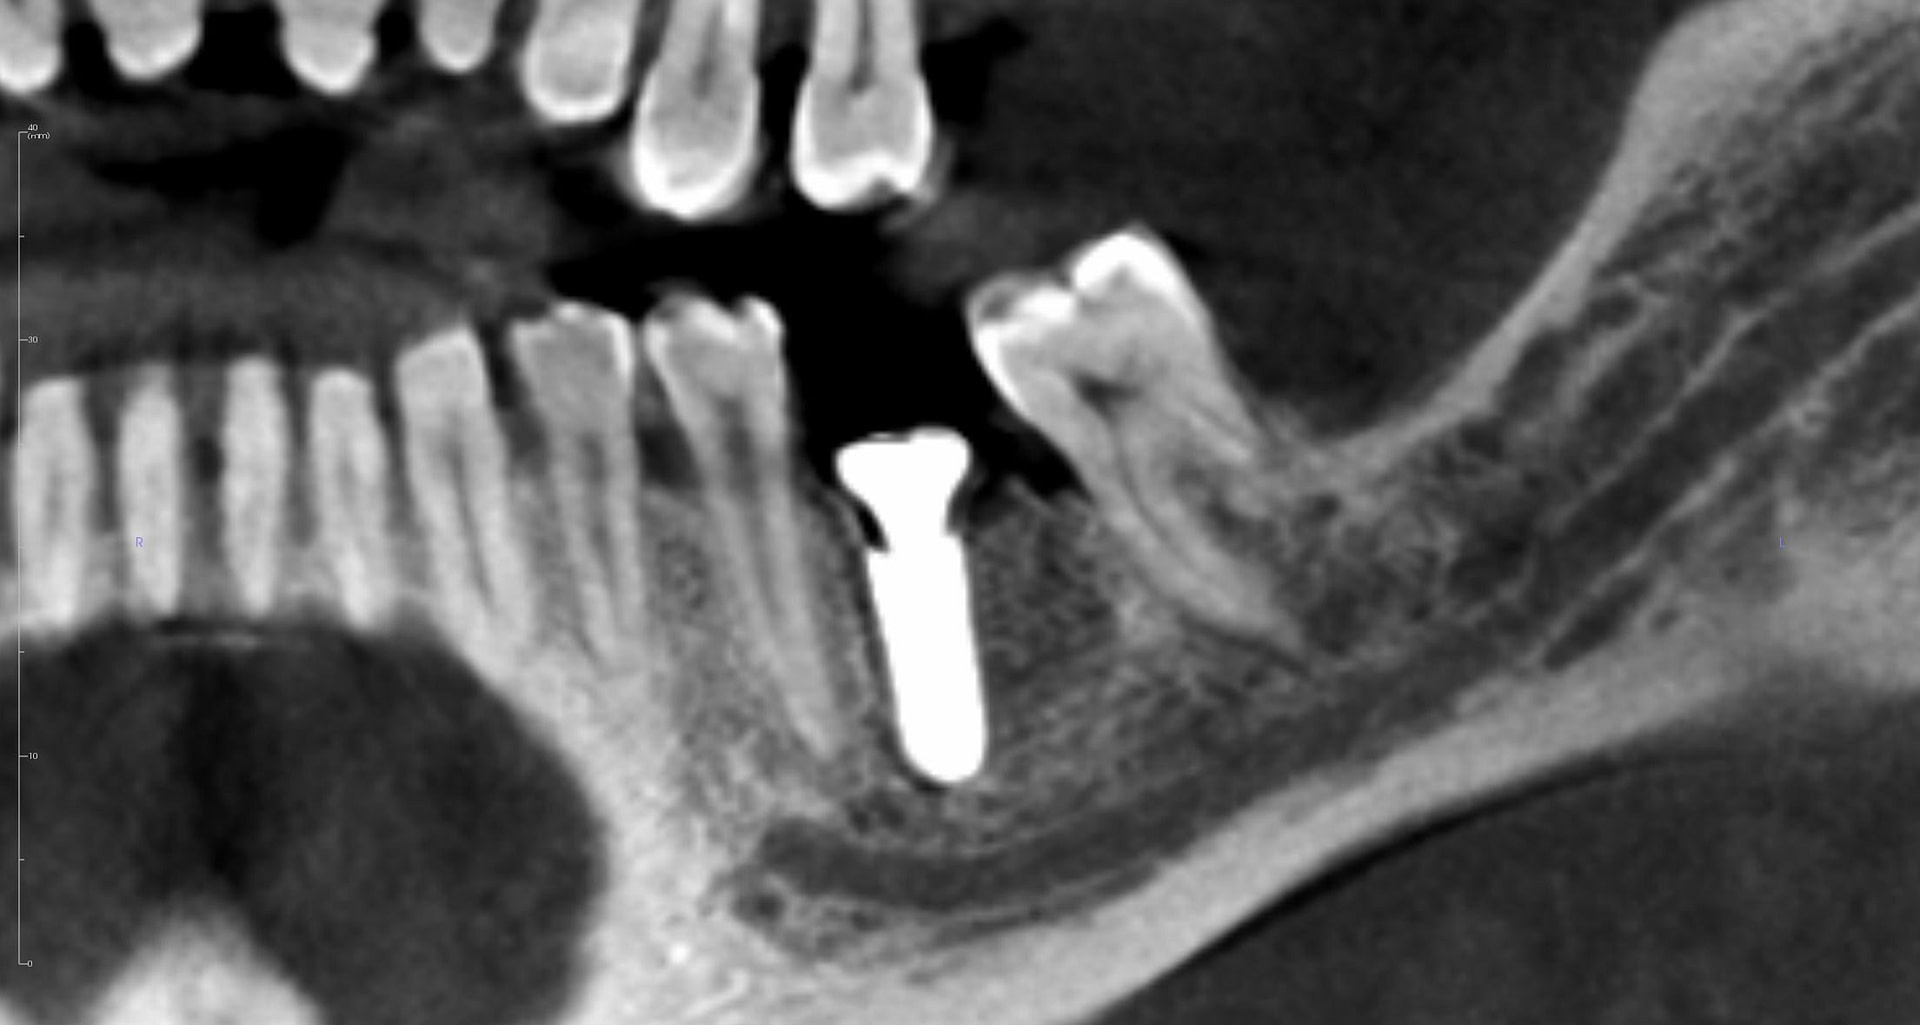

Two implants placed using the X-Guide System by Dr Ashish Gulati at iDD. The results are excellent.